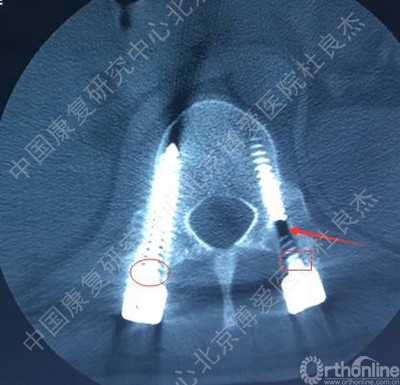

伤后当天在全麻下行“后路探查减压复位椎弓根钉内固定植骨融合术”。手术后给予综合治疗,患者双下肢肌力较术前好转,但仍存在无力及感觉异常,大小便功能无明显改善。为进一步康复治疗及训练就诊中国康复研究中心北京博爱医院,以“腰椎骨折术后并脊髓损伤”收住院。患者近期精神、饮食、睡眠好,小便留置尿管,大便需借助开塞露。

辅助检查

3、胸12椎弓根钉断裂

1.手术失败的原因?